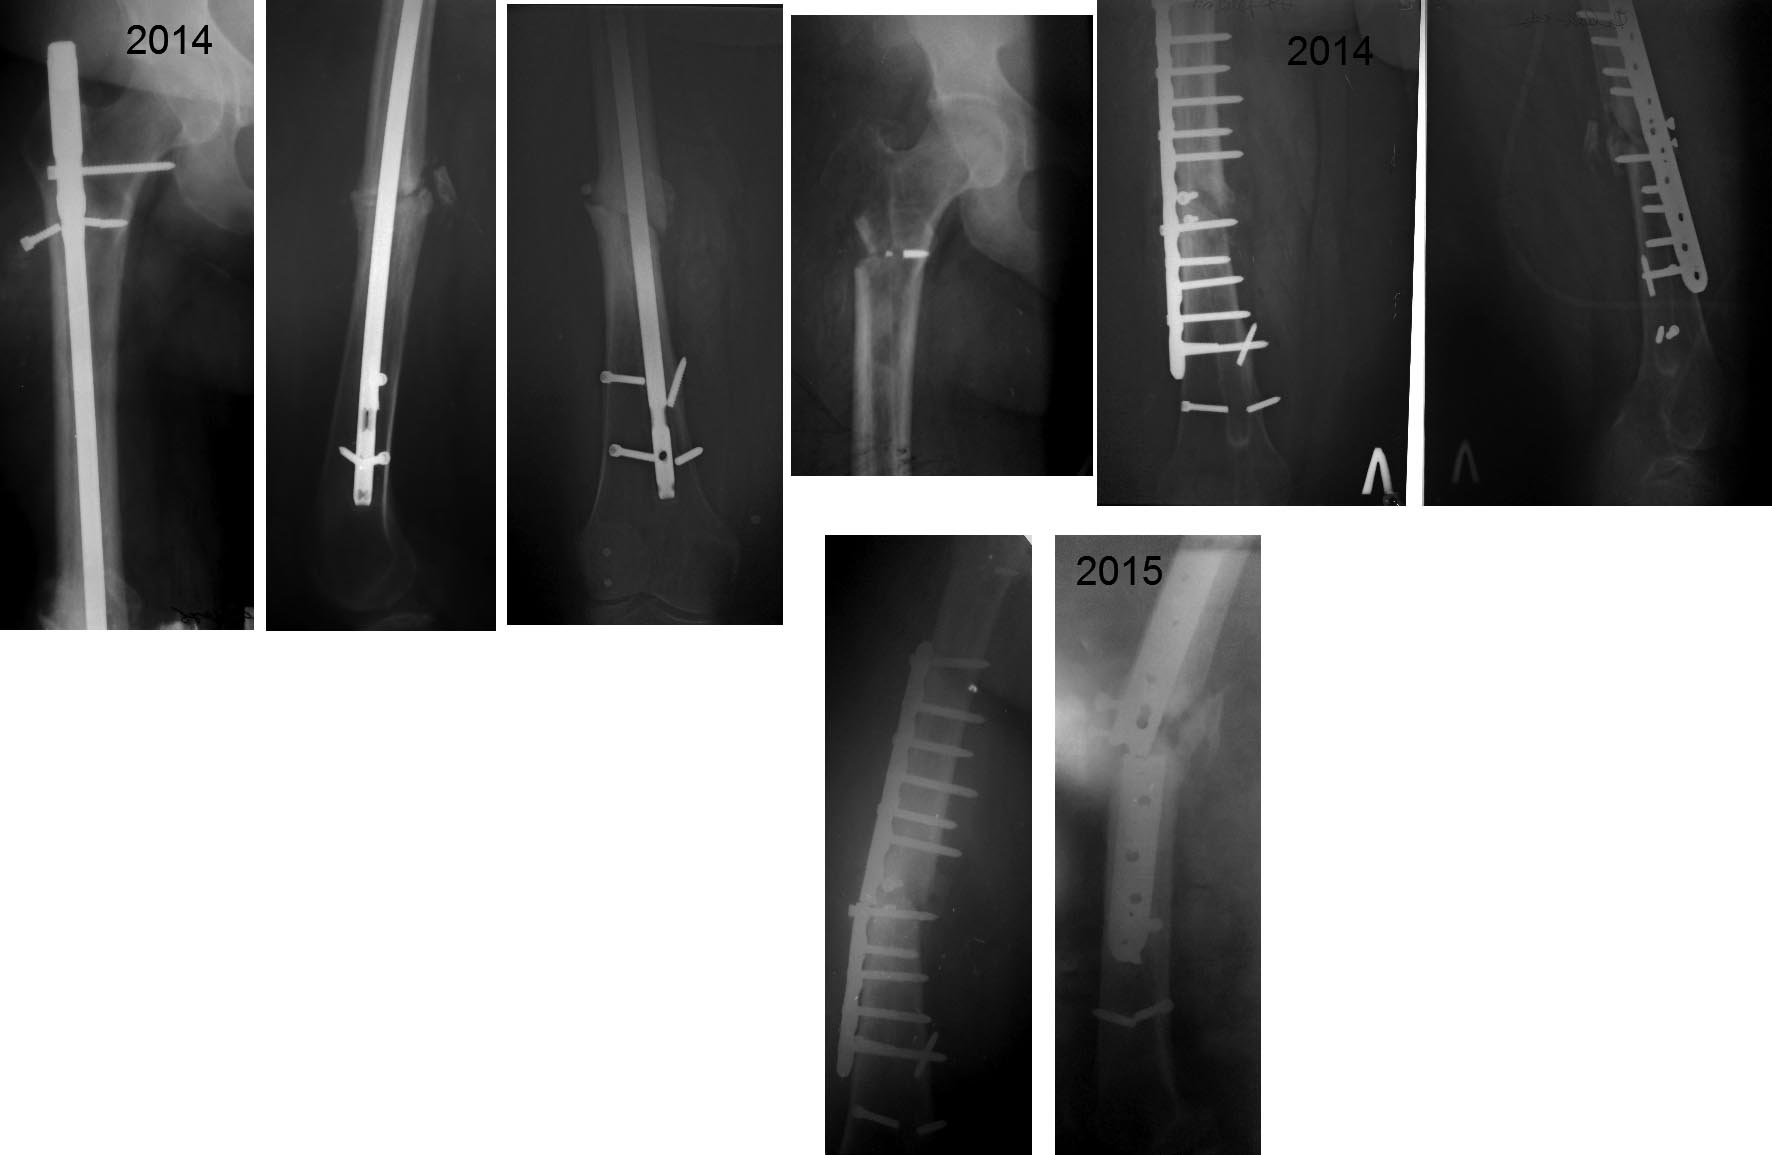

Здравствуйте уважаемые коллеги, прошу поделиться опытом лечения подобных пациентов. Пациентка К.40 лет ,вес- 130кг, рост 170 см, курит, С.Д. 2 тип-компенсированный.Травма в рез. ДТП 2008 г.- БИОС.Август 2014 г.-удаление стержня (судя по снимку с немалыми трудностями),костная аутопластика, МОС пластиной –заживление первичное. Поступила 29 09 2015 с несращением перелома и переломом фиксатора. СОЭ-16, Лейк-11.0.Предварительный план обследования и лечения:1.Исключить(подтвердить) наличие инфекции. Какой алгоритм, в сомнительных случаях, используете Вы? 2.Фиксация перелома длинной Gamma или PFNа с (или без) антибактериальной мантией (склоняемся к данному методу, однако настораживает потенциальный риск инфекции).3.Аппаратный метод лечения (со своими достоинствами и недостатками).Благодарю за помощь в принятии решения .С Уважением, Накоренок Илья.

Основанием выбора Гамма/PFN и т.п.являются:

1.Уже имеющееся, избыточно латеральное для стандартных стержней, место введения.

2.Скомпрометированная(после удаления стержня) подвертельная область(снимок 4)

Гамма/PFN имеют дистальные динамические отверстия,соответственно "динамика" вполне возможна.